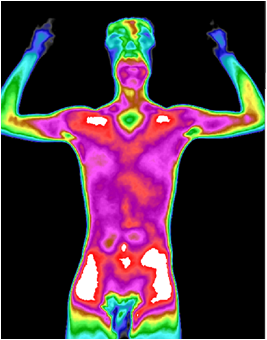

图1 肠道功能失调红外热成像图

红外热成像非常灵敏,它能极其敏感地接收人体细胞新陈代谢所产生的热辐射(小于0.025 ℃ ),并通过特有的成像和“由表及里”的病灶凸显层析技术,显示出人体内异常热源的分布、深度、强度、形态及走势。从而全面、真实、动态地反映由人体代谢热所表达的健康状况和疾病信息,再与其他技术手段结合,有利于临床作出更加真实、准确、早期的诊断和疗效评估。

图3 颈肩肌肉劳损红外热成像图